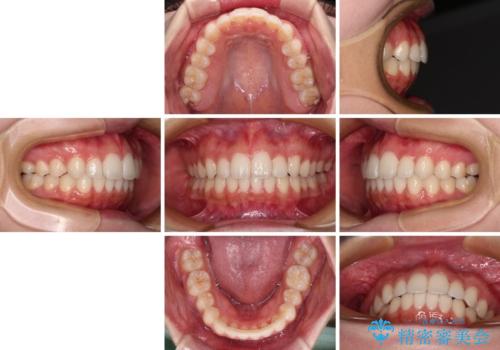

インビザライン特有の、奥歯の咬み合わせの問題もなく、しっかりと歯列を改善することができました。

舌側転位している上顎側切歯(内側に引っ込んでいる真ん中から2番目の歯)は、インビザラインが最も移動を苦手とする歯であり、これ以上の改善を望まれる場合にはワイヤー矯正、あるいはワイヤー矯正の併用をお勧めいたします。